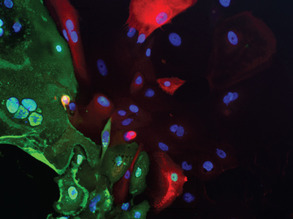

Illuminating MS